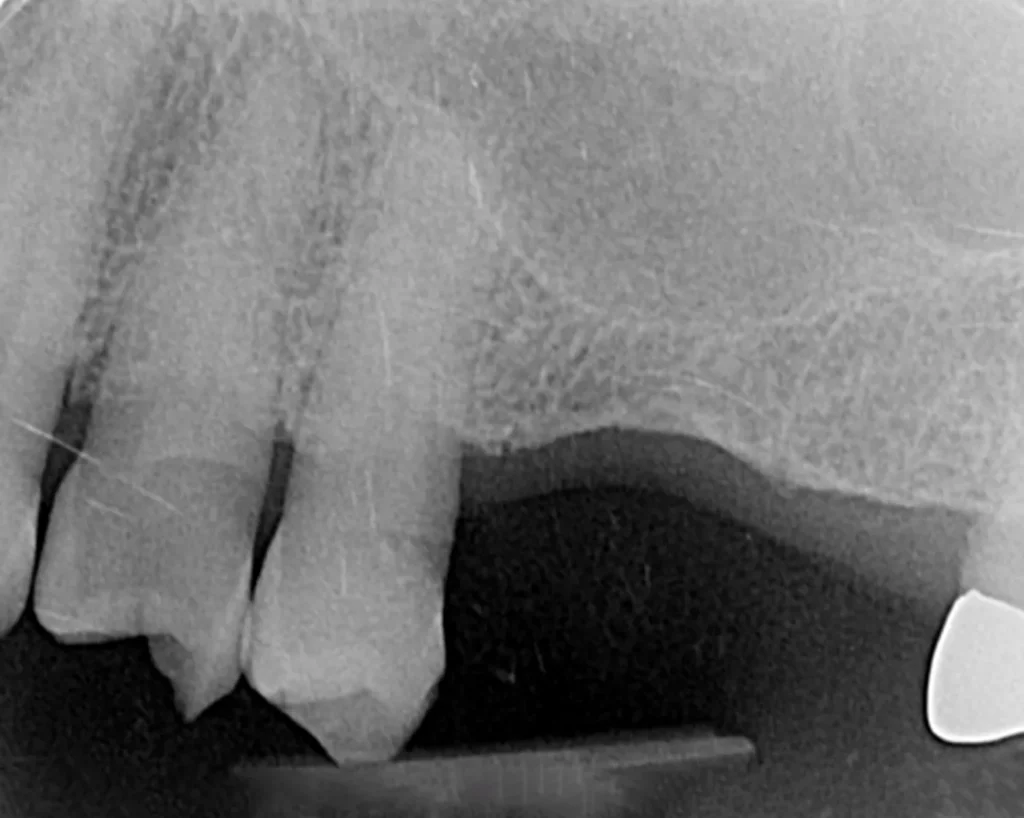

This lady attended Gentle after a previous implant had not worked. In the left photo below is a temporary bridge that kept falling out, which was frustrating for the patient, so she wanted to try again with implant treatment. Moreover, when she smiled, the adjacent eye tooth had an exposed root, so it looked too long. At the same time as placing gum around the implant, a gum graft was placed to cover the exposed eye tooth root. This improves the overall aesthetic outcome for the patient. Below on the right you can see how we took time to rebuild the bone and gum in the first phase of treatment, which gave the implant a solid foundation to sit in.

The implant was placed into the bone, under the gum, and a white post was chosen to fit into the implant to maximise the final crown’s appearance. The after photo was taken 5 years after the implant was placed and shows how nicely the work is performing.